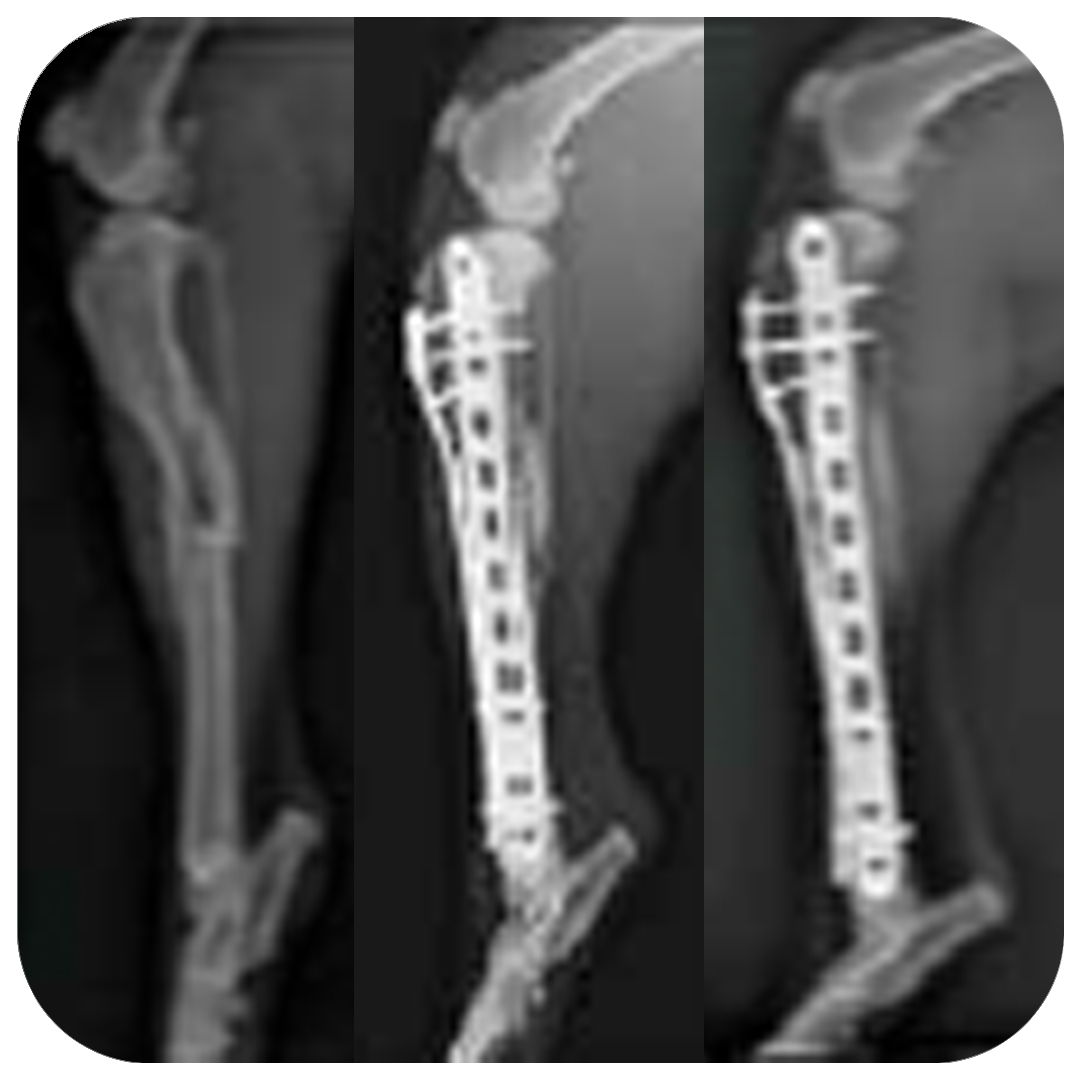

Ella’s recovery from a broken leg has been remarkable and owners, Eileen and Hannah are amazed by how quickly Ella’s injury has healed.

“I do believe that the light therapy has played an important part in Ella’s progress. The bruising and swelling went quickly after starting the daily light treatment.”

At her 9 week post-operation check up the vets and orthopedic surgeons used the words; ‘outstanding recovery’. Hannah couldn’t recommend HeaLED enough; “The bone has healed nicely and she is doing so well. I am so pleased and hopefully Ella will be able to get back to her Agility competitions soon!”

Right tibial and fibular fracture

• Traumatic mid-diaphyseal comminuted fracture of the right tibia and transverse fracture of the mid-diaphysis of the fibula.

• Fracture stabilised by bridging fixation using a 12 hole 3.5mm LCP plate medially and a 16 hole 2.7mm LCP plate cranially. -